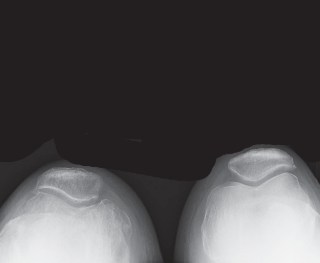

Diagnostic Imaging Modalities

High-quality, standardized, weight-bearing radiographs are the cornerstone of preoperative planning. A standard knee series must include a weight-bearing anteroposterior (AP) view, a weight-bearing lateral view in extension, and a skyline (Merchant) view of the patella. The AP view reveals joint space narrowing, subchondral sclerosis, osteophyte formation, and the presence of subchondral cysts. The lateral view is essential for assessing patellar height (Insall-Salvati ratio) and the posterior slope of the tibia.

Crucially, we must obtain a 45-degree posteroanterior (PA) weight-bearing view (the Rosenberg view). Because cartilage wear in early-to-moderate OA predominantly affects the posterior aspect of the femoral condyles, the standard extension AP view may falsely appear normal. The flexed Rosenberg view unloads the patella and brings the worn posterior condyles into contact with the tibia, revealing hidden joint space narrowing. Furthermore, a full-length, hip-to-ankle standing radiograph is highly recommended, particularly in patients with severe deformities or a history of prior femoral/tibial fractures, to accurately determine the mechanical axis and identify any extra-articular deformities that might complicate intramedullary instrumentation.